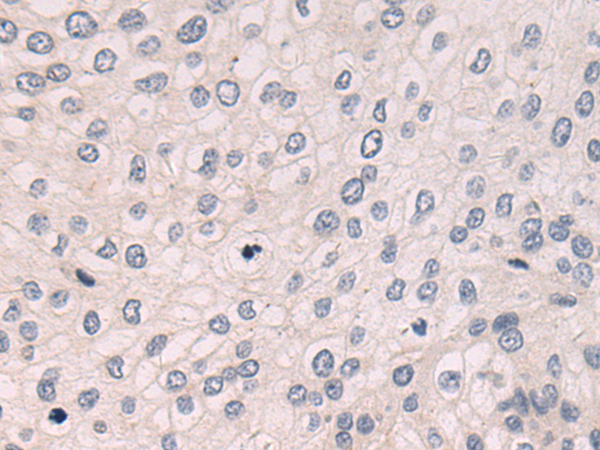

分类: 科研抗体货号: P08400别名: KMT7; SET7; SET9; SET7/9应用: IHC反应种属: Human, Mouse